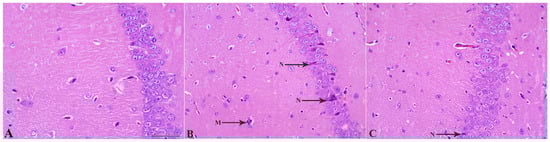

2.4. MSCs Prevent LPS-Induced Neuronal Loss

2.8. MSC Treatment Attenuates LPS-Induced Astrocytic Hyperplasia and Hypertrophy